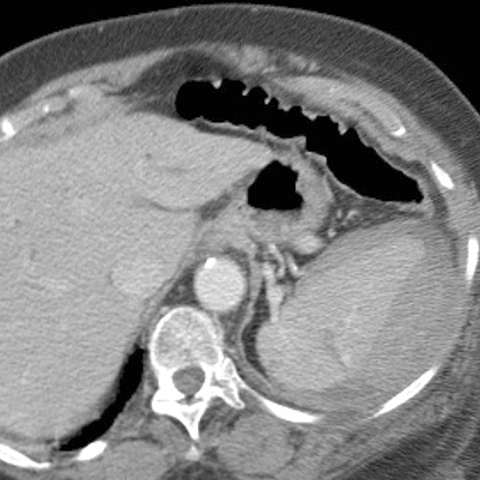

23-year-old male presents with blunt abdominal trauma after a motor vehicle accident [1 of 3]